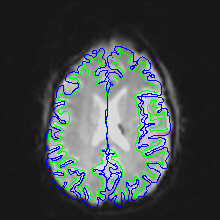

A qualitative way of judging the effectiveness is to overlay the unwarped EPI on the T1 and see how they match. Here are corrected EPI images with the gray and white matter boundaries overlaid.